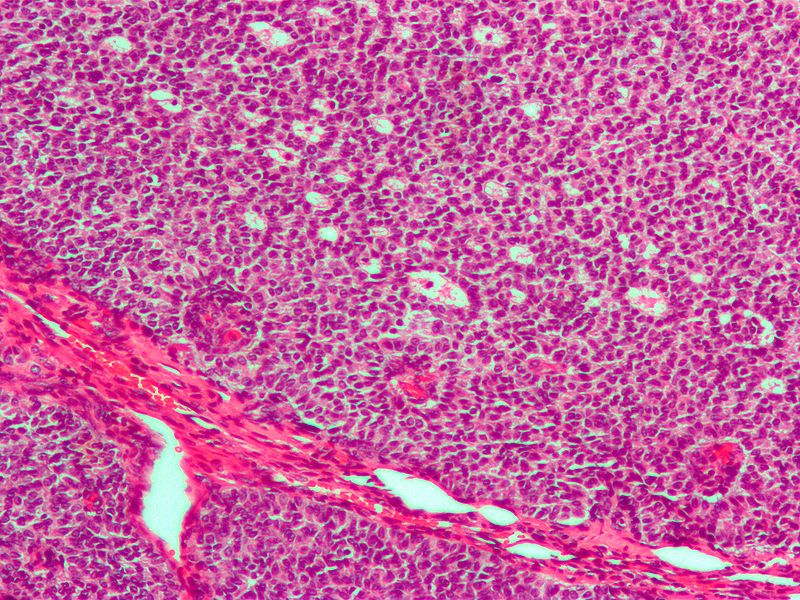

Large cells with transparent cytoplasm and central nuclei (like spermatogonia) make up the malignant tumor known as a seminoma, which develops as a homogeneous mass without bleeding or necrosis.